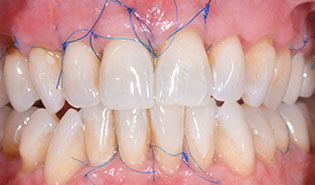

3.2 Immediate Load Prosthetics (All-on-4)

This part of the course covers the methods of diagnosis, practical treatment planning, pre-surgical prosthodontics, imaging, armamentarium, and clinical techniques needed for this exciting treatment modality. Crucial to this treatment modality is the understanding of the biomechanical aspects and functional loading of the immediate full arch prostheses. The aesthetic and phonetic requirements, space requirements, laboratory communication, insertion techniques post-operative follow-up and hygiene requirements are key to this treatment.

Prosthetic restoration - impressions, registration and

jaw relationships